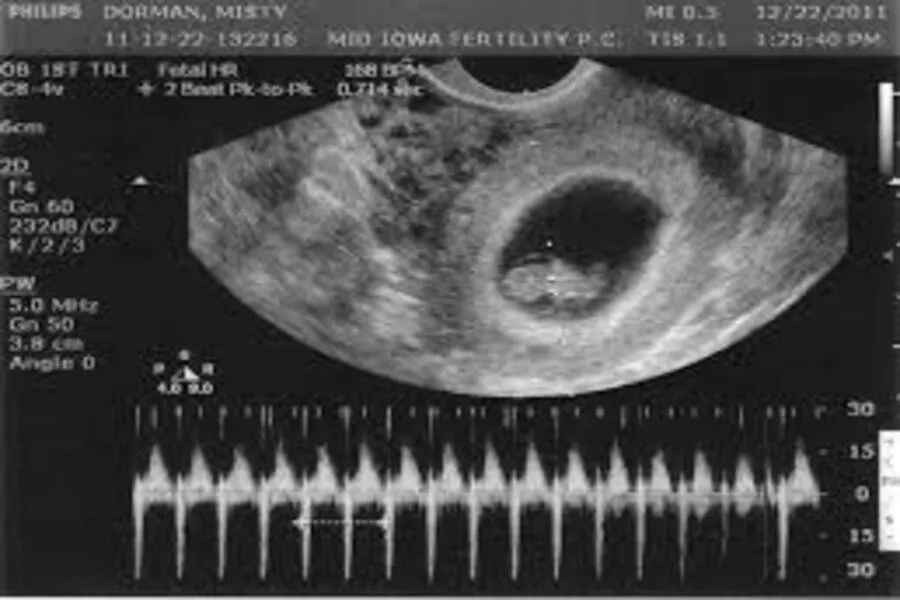

2. Beta hCG vượt ngưỡng nhưng túi thai chưa vào tử cung

Khi nồng độ này đã vượt mức 1.500–3.000 mIU/mL nhưng siêu âm đầu dò chưa thấy túi thai trong buồng tử cung, bác sĩ sẽ nghi ngờ thai ngoài tử cung hoặc thai chưa vào tử cung. Trường hợp này cần theo dõi chặt chẽ bằng xét nghiệm và siêu âm lặp lại sau 48–72 giờ để đưa ra kết luận chính xác, vì thai ngoài tử cung nếu không xử lý kịp thời có thể gây xuất huyết trong ổ bụng và đe dọa tính mạng mẹ.